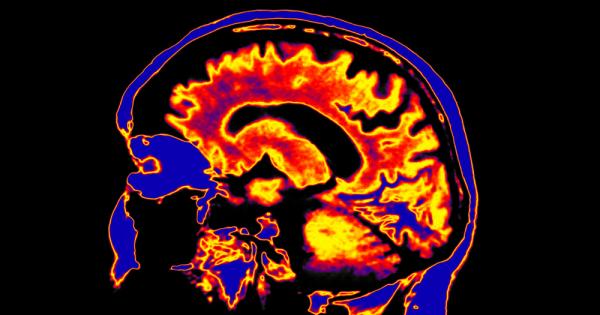

Структурата Мозъка - Новини